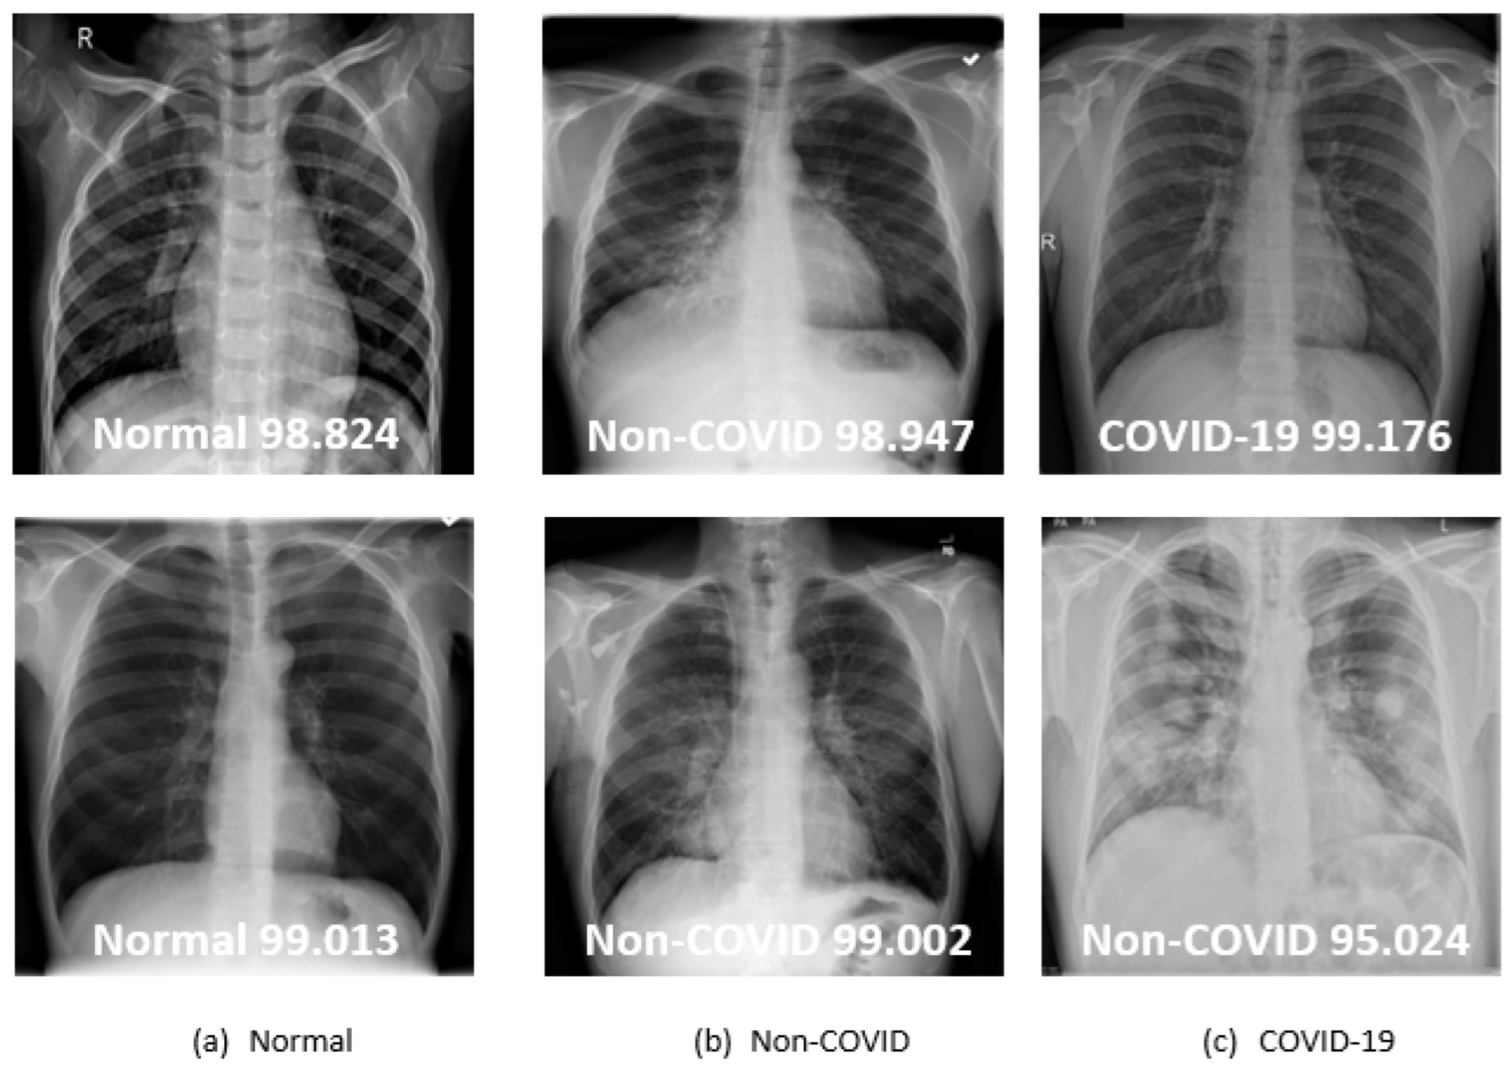

Figure 12 shows results from the hybrid DCNN mechanism on some sample instances from the test set. For example, the proper category kind, shown in Figure 12a top/bottom, is accurately diagnosed with a probability greater than 98.82% as “Normal”. Moreover, the suggested strategy accurately identifies each instance in Figure 12b (top/bottom images). The proposed mechanism is accurately identified, as shown in the top image of Figure 12c. In contrast, the irregular opacity of the lungs affects the feature extraction process. So, erroneous lung disease identifications may arise, as illustrated in Figure 12c (bottom image). Considering the outcomes, it can be deduced that the recommended hybrid DCNN mechanism enhances the accuracy of COVID-19 disease identification. Specifically, combining the highly effective first four blocks of the VGG19 architecture with the efficient inception modules allows our network to capture useful features missed by other methods, thereby reducing the frequency of inaccurate identifications.

Figure 12. Indicative instances evaluated by hybrid DCNN mechanism.